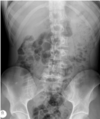

This abdominal X-ray demonstrates multiple dilated loops of bowel with clear valvulae connivente markings. The large bowel is collapsed. **This indicated small bowel obstruction.**